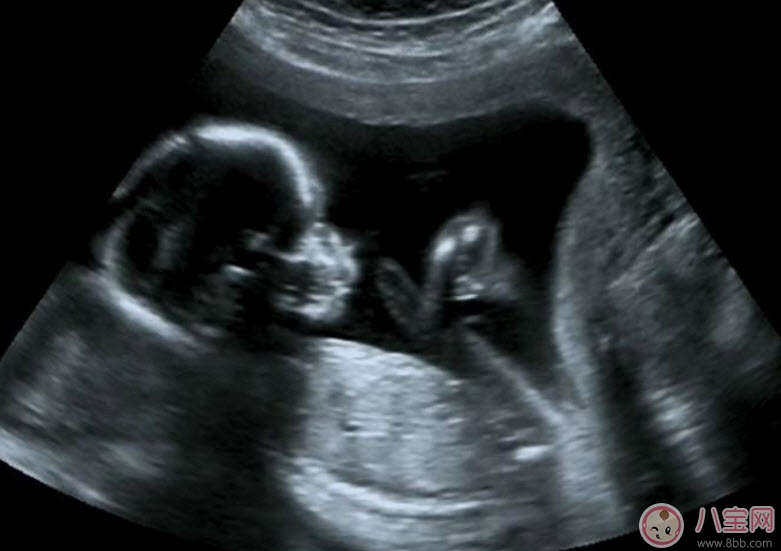

孕早期阴道B超对胎儿有影响吗相信这是准爸妈们最关心的问题 。一般认为B超是一种声波传导,不存在电离辐射和电磁辐射,对人体组织没有什么伤害 。

事实上,医学使用的B超是低强度的,低于安全阈值;早孕期检查的时间短,一般不超过3分钟,并且是非定点的滑行检查,对胚胎来说是基本安全的,至今尚没有B超检查引起胎儿畸形的报道 。